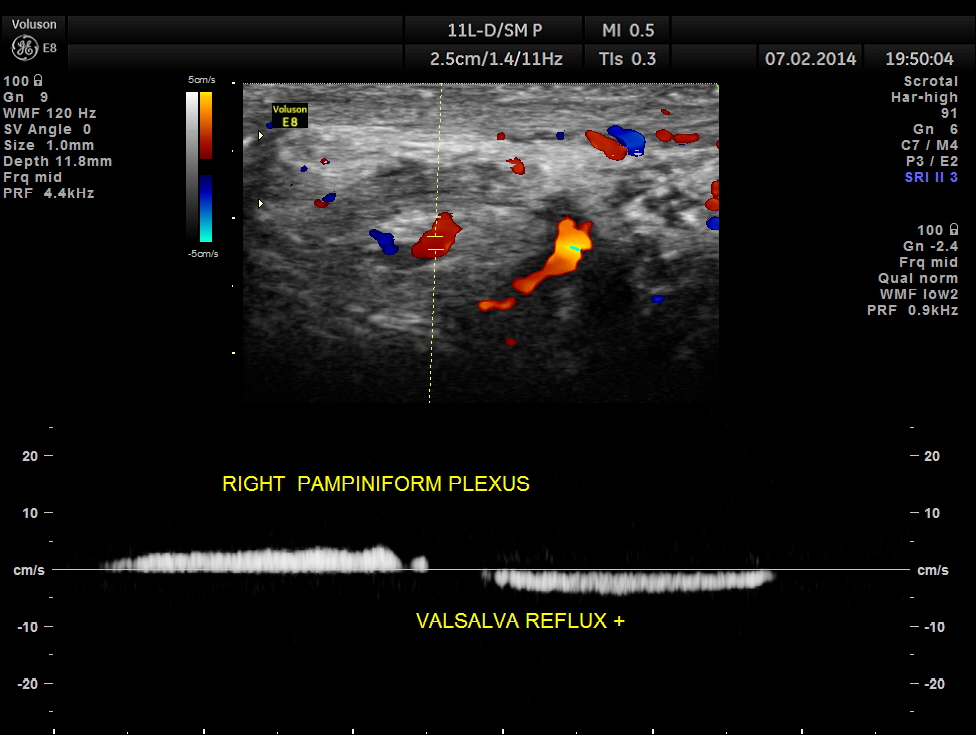

Right pampiniform plexus also showed dilated veins with reflux.

Spectral doppler shows reversal of flow .